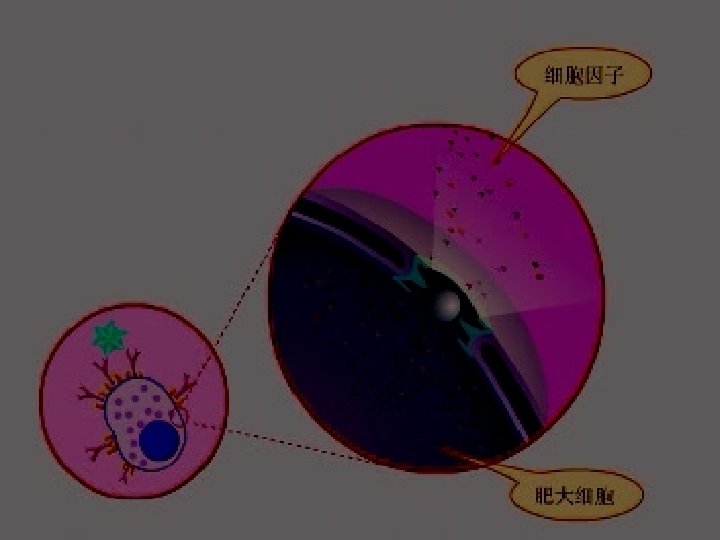

Pathology: Type allergy Allergic inflammation: Predominant T cells & eosinophilic cells infiltrate.